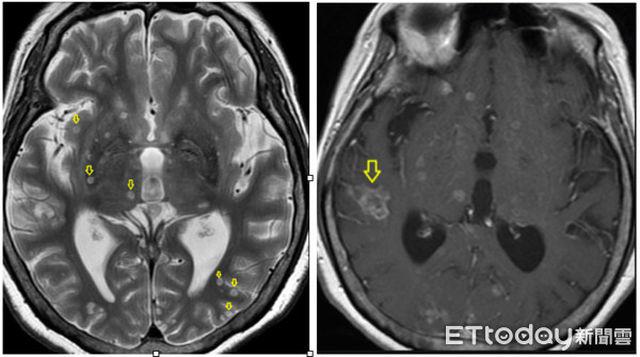

Hình ảnh "tổ giun" trên não bà Tiêu

Một người phụ nữ 68 tuổi đột nhiên bị bất tỉnh, được gia đình đưa đi cấp cứu. Người phụ nữ họ Tiêu nhập viện trong tình trạng sốt, viêm áp xe phổi, đường huyết cao và teo não nhẹ. Sau 7 ngày, tất cả các triệu chứng đã được kiểm soát và ổn định, nhưng đột nhiên bà Tiêu lại rơi vào hôn mê. Bác sĩ tiến hành kiểm tra cộng hưởng từ não và bất ngờ phát hiện ra trong não của bà Tiêu có một “tổ giun”, chứa đầy ký sinh trùng gọi là bệnh ấu trùng sán lợn do ấu trùng Cysticercus cellulosae gây ra.

Bác sĩ Hứa Nguyên Dục, trưởng Khoa X-quang của Bệnh viện Từ Tế, Đài Bắc, Đài Loan cho biết, bệnh nhân nói rằng, nửa năm trước bà đã ăn thịt lợn sống khi đi du lịch ở Đông Nam Á, đây chính là nguyên nhân dẫn đến bà bị bệnh ấu trùng sán lợn, bởi cysticercus là một loại ký sinh trùng có nguồn gốc từ lợn. Đội ngũ y tế xác định tình trạng của bà Tiêu là kết quả của ký sinh trùng trên cơ thể lợn chuyển vật chủ, bệnh nhân nhanh chóng được điều trị bằng thuốc chống ký sinh trùng. Sau 40 ngày điều trị ở viện, bà Tiêu đã được xuất viện thuận lợi.